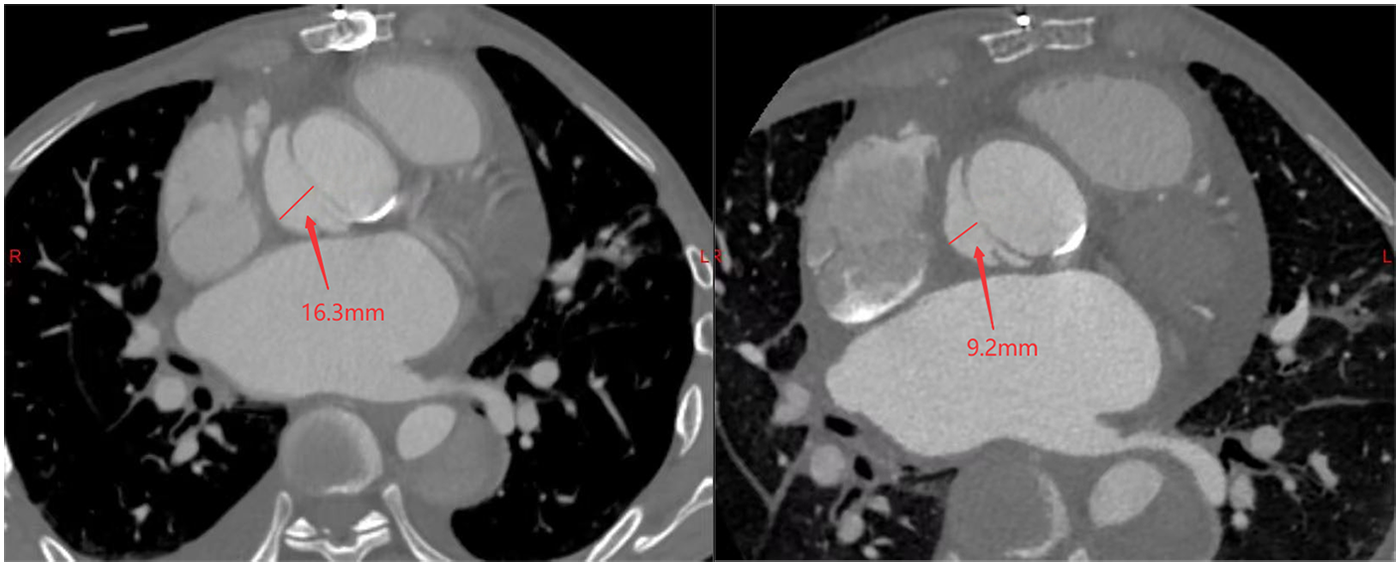

A 38-year-old male with Marfan syndrome underwent Bentall + Sun's surgery for aortic dissection. Three months later, he was readmitted with exertional dyspnea. Echocardiography confirmed a paravalvular leak with high-velocity flow across the defect into the right atrium via a surgically created shunt, resulting in heart failure. The patient declined reoperation. Multimodal imaging—including echocardiography (Figure 1, Supplementary Video S1) and computed tomography (Figure 2, Supplementary Video S2)—was used to plan transcatheter PVL closure.

Figure 2

Pre-procedural (left) and post-procedural (right) CT scans demonstrating the pseudoaneurysm at its maximum width.

Post-procedural echocardiography (Figure 1, Supplementary Video S3) showed minimal residual leak. Follow-up CT (Figure 2) demonstrated significant reduction in pseudoaneurysm size. No complications—such as hemolysis, device migration, new PVL, or recurrent heart failure—were observed. The outcome was satisfactory.